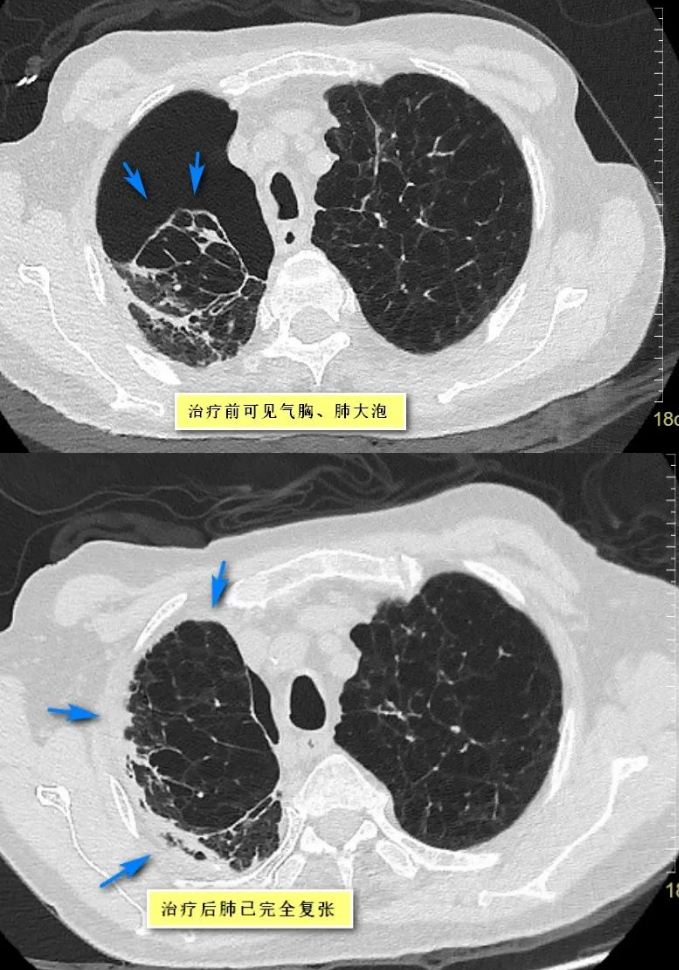

经过与李伯和家属的沟通,呼吸与危重症医学科团队为李伯进行了胸膜固定术。“治疗过后,患者气胸引流管漏气量逐渐减少,气促症状逐渐缓解,手术很成功!”廖槐告诉记者,2023年12月7日,CT复查显示李伯的肺已完全复张,能够顺利地拔除胸腔引流管。很快,李伯便痊愈出院了。

CT显示李伯的肺经治疗已经完全复张